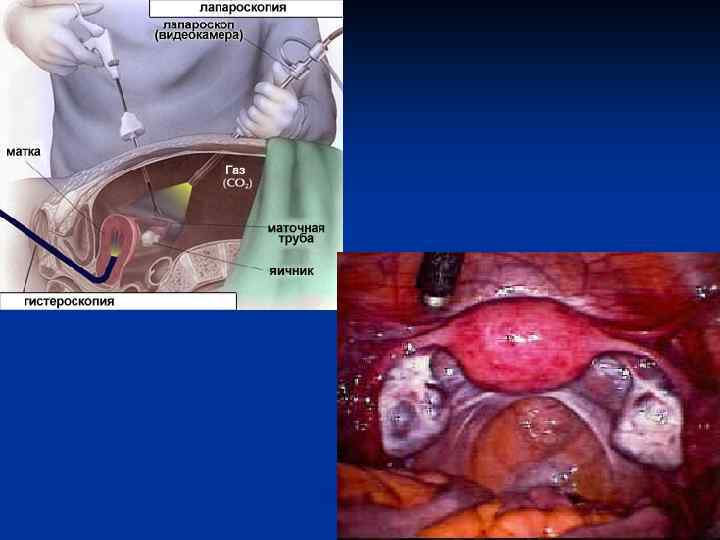

Женские половые органы, organa genitalia feminina

Женские половые органы, organa genitalia feminina